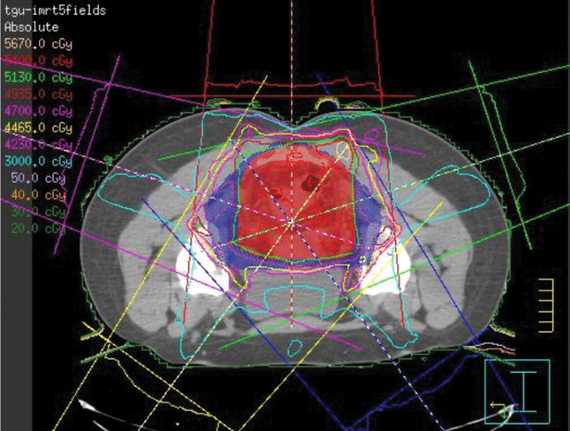

Dosimétrie

Voici un aperçu d’un plan de dosimétrie élaboré à partir d’une image de scan de planification. On y voit les régions à traiter et celles à protéger ainsi que la distribution de la dose et les points d’entrée des faisceaux de radiation.